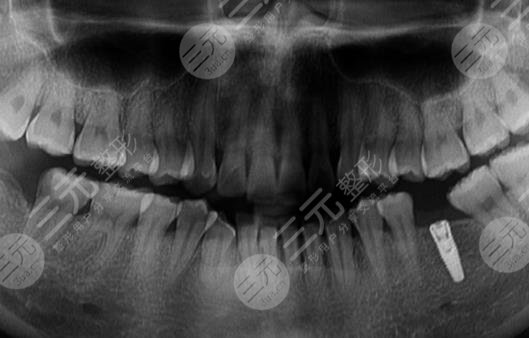

后来在朋友的介绍下,我来到宿州信美口腔医院(淮海中路)做面诊,医生说现在医疗科技较为发达,种植牙既可以解决这一问题,而且他建议我种植牙做的越早越好,如果做太晚的话牙龈萎缩,往后再想做种植牙就会比较麻烦。况且牙齿缺失以后,会对人体的健康造成巨大的影响,人体本身就是一个比较复杂的机制,如果牙齿出现了问题,就会影响肠胃等。综合考虑后,我决定接受医生的建议,做种植牙。

种植牙主要分为两大部分,第1个则是牙根的植入,牙根采用的是和人体骨骼能相容的钛合金,所以植入以后不会产生任何的排斥反应,而牙冠则采用和牙齿坚硬程度差不多的合规材料来做。整个过程并不是一蹴而就的,前前后后我也去医院多次,每次去都能感觉到这里医生护士的用心,这消除了我看牙的恐惧。

种植牙虽然前后要进行多次操作,不过每次操作时间并不长,在植入牙冠之时仅用了半个小时就好了,而植入牙冠是在麻醉的状态下进行的,所以看牙的时候也没有明X的痛感,对此我较为的满意。两个月以后,整个步骤都全部完成,而我也补上了此前缺失的牙齿,牙齿补上以后,我整个人都自信了许多,讲话不再漏风,咀嚼吃东西也更加的利索,对此我较为的满意。在这里要劝大家,如果牙齿有问题的话,一定要第一时间到专业机构去做诊疗,不要一拖再拖,这样会造成严重的后果。